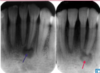

What is this radiographic & clinical findings?

Periapical cyst

shows inflammation at site

abscess developed fistula tract thru

soft tissue. Pt will have pain until

pressure is released